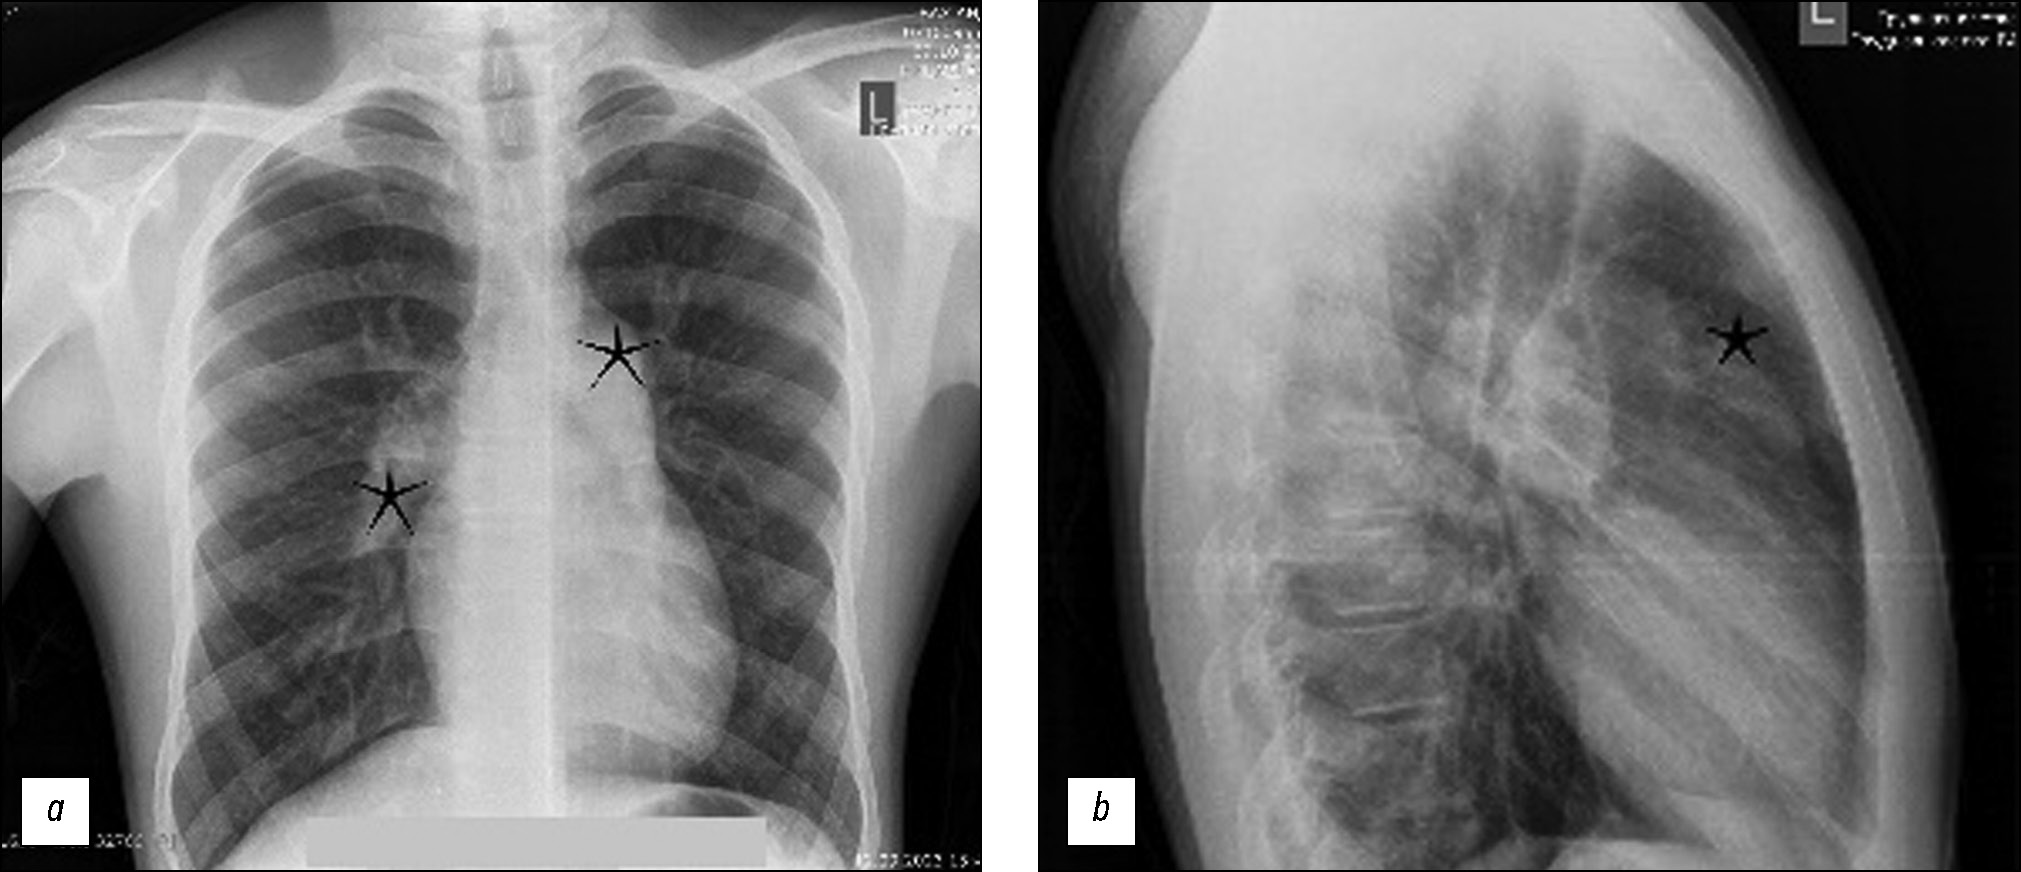

Pulmonary artery pseudoaneurysm in a young man with pulmonary hypertension on computed tomography angiography

Abstract

Pulmonary artery aneurysms and pseudoaneurysms are uncommon anomalies; however, their associated morbidity underscores the importance of recognizing them. Herein, we present a clinical case involving a 15-year-old male patient who presented at our clinic with complaints of hemoptysis. Upon diagnosis, a left lung aneurysm was found. Subsequent computed tomography angiography and intervention on the pulmonary arteries confirmed the presence of pulmonary artery aneurysms, elucidating that the hemoptysis was caused by the rupture of the aneurysm. The intervention on the pulmonary artery further confirmed the diagnosis. Early detection and management of pulmonary artery aneurysms are crucial, particularly in young patients, as timely intervention can prevent severe complications and improve patient outcomes. Raising awareness of these vascular abnormalities and promptly addressing them through appropriate diagnostic measures and interventions can help healthcare providers effectively mitigate the potential risks associated with pulmonary artery aneurysms, thereby enhancing patient care and prognosis.